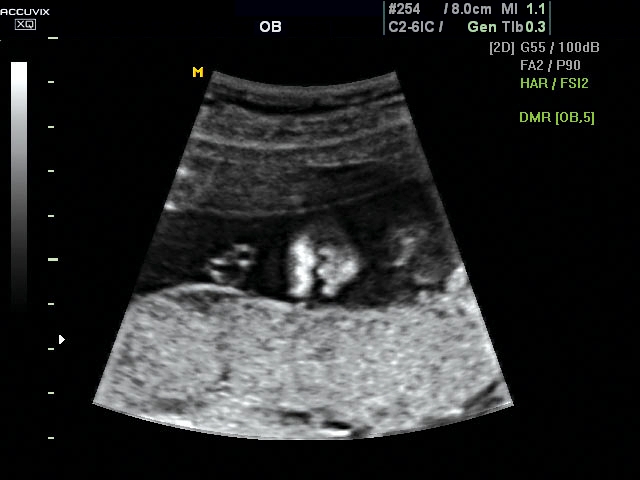

A pontos analízis és diagnózis iránti egyre növekvő igény kiszolgálására a MEDISON egy új real time képfeldolgozó technológiát fejlesztett ki Dynamic MR™ elnevezéssel. Az eljárás a diagnosztikus ismeretanyagot a precizitás és a pontosság egy teljesen új szintjére emeli. Használata az alapvető 2D ultrahang képinformáció real time, kivételesen kristálytiszta és kiemelkedően részletezett megjelenítését teszi lehetővé tűéles kontúrok és finoman rajzolt szövetstruktúra mellett. A DMR™  technológia ideális eszköze az ultrahang-diagnosztikának kezdve a szülészet-nőgyógyászattól a foetalis echon át az általános alkalmazásokig.

Magzati koponya képe normál 2D módbanMagzati koponya 2D képe bekapcsolt Dynamic MR funkcióvalMagzat törzsének képe normál 2D módbanMagzat törzsének képe bekapcsolt Dynamic MR funkcióvalMagzat felsőajakjának és orrának képeMagzat felsőajakjának és orrának képe bekapcsolt Dynamic MR funkcióval

A DynamicMR alkalmazása az átlagos ultrahang teljesítményt a zaj és szemcsézettség jellegű műtermékek kiszűrése révén a vizuális diagnosztika, a precizitás és a pontosság új szférájába emeli. Figyelje meg a cerebellum, CSP és cisterna magna élstruktúráit, mennyire pontosan definiáltak és a teljes agyi struktúra ábrázolása a Dynamic MR alkalmazásával milyen látványosan javul.